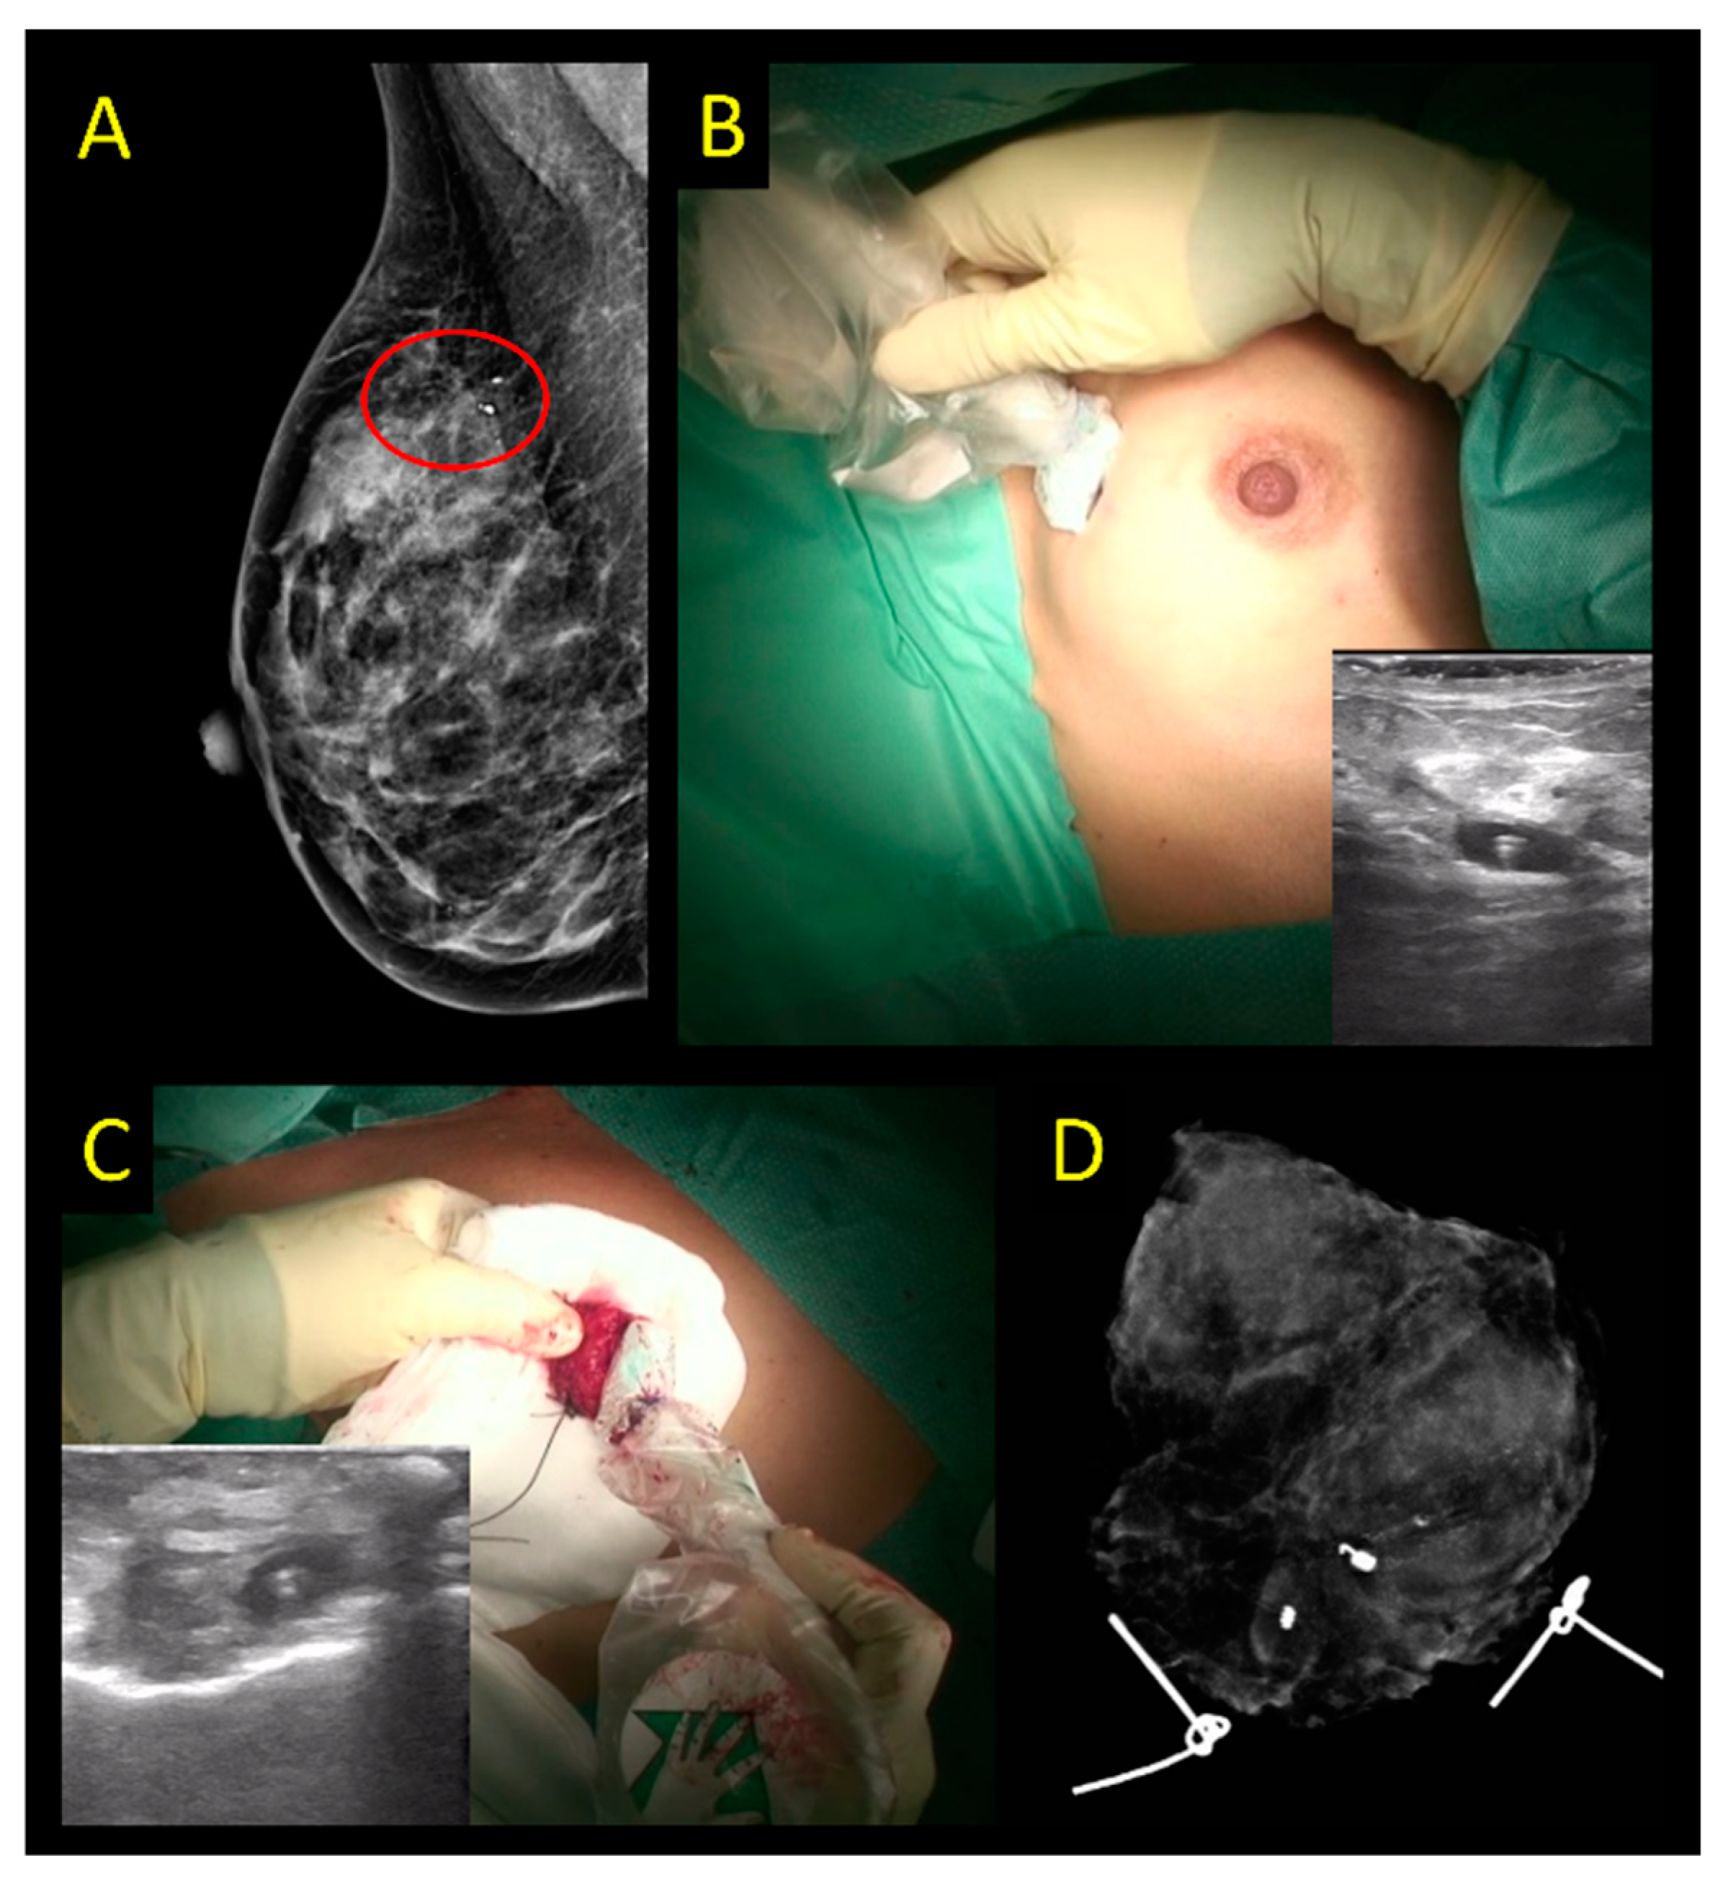

2.1. Wire-Guided Localization (WGL)

| Successful Excision | Positive Margins 1 | Re-Operation Rate | Data Quality | |

|---|---|---|---|---|

| Wire-guided localization (WGL) | 99% [9,12] | 15–21% [9,10,12,14] | 14–19% [9,10] | High; Meta-analyses of RCTs available (LoE 1a) |

| Radioactive seed localization (RSL) | 100% [9] | 12–13% [9,10] | 10–15% [9,10] | High; Meta-analyses of RCTs available (LoE 1a) |

| Radio-guided Occult Lesion Localization (ROLL) | 99.5% [9] | 12–17% [9,10] | 9–10% [9,10] | High; Meta-analyses of RCTs available (LoE 1a) |

| Magseed | 99.8% [12] | 13.3% [12] | 12% [12] | Large cohort studies [12], no RCTs (LoE 2b) |

| Sirius Pintuition | 100% [15] | 8% [15] | 4% [15] | Small cohort studies, one small RCT 3 [15] (LoE 2b) |

| MOLLI | 100% [16] | 0% [16] | 0% [16] | Small phase I cohort study (LoE 4) |

| TAKUMI | 100% [17] | 7.3% [17] | 4.9% [17] | Small cohort study (LoE 4) |

| SAVI SCOUT | 99.64% [4] | n.d. | 12.8% [4] | Systemic review and pooled analysis [4] (LoE 2b) |

| LOCalizer | 99.9% [18] | n.d. | 13.9% [18] | Systemic review and pooled analysis [18] (LoE 2b) |

| EnVisio | n.d. | n.d. | n.d. | Case report [19] (LoE 5) |

| Intraoperative ultrasound (IOUS) | 100% [8] 2 | 5% [8,10,11] 2 | 5–7% [8,10] 2 | High; Meta-analyses of RCTs available (LoE 1a) 2 |

| Carbon | 79.0–99.1% [20,21,22,23,24] | 75.0–96.4% [21,22,25] | 7.1% [25] | Cohort studies, no RCTs (LoE 4) |